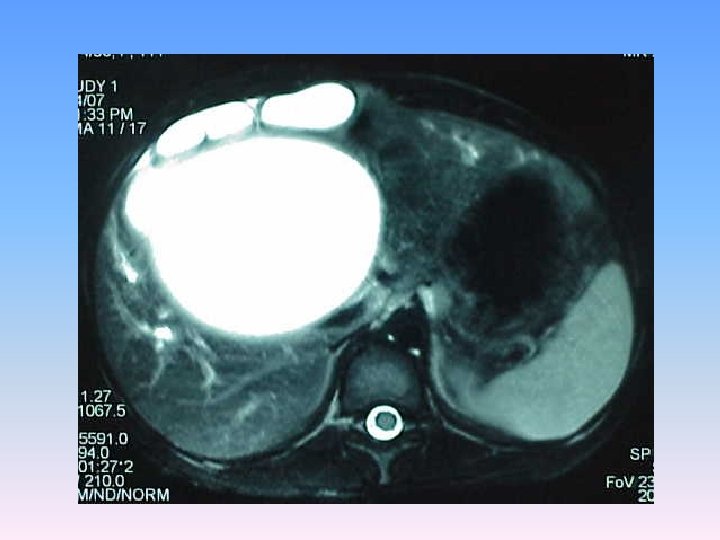

MRCP & MRI § Huge thicked wall cystic mass (140 x 120 mm), at the portahepatis that seems connected to biliary tree and gall bladder, resulted in severe dilatation of intra hepatic bile ducts and displaced right kidney posteriorly. § Spleen, kidneys, bowel loops and abdominal wall are normal. § Finding could be due to congenital anomalies like choledocal cyst, Duplication cyst, mesenteric cyst and hydatid cyst are in DDx.